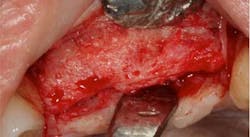

Fig. 2